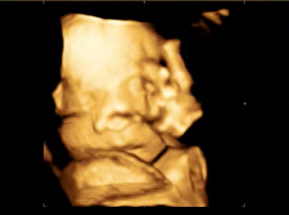

ps.사진은 입체초음파에서 하품할때 찍힌영상인데

너무귀여워서 올려봐요ㅋㅋ제 뱃속에서 소변도 보고 딸꾹질에 하품도 하고 너무 신기해요

귀여워라~~ 하품을 하다니♡